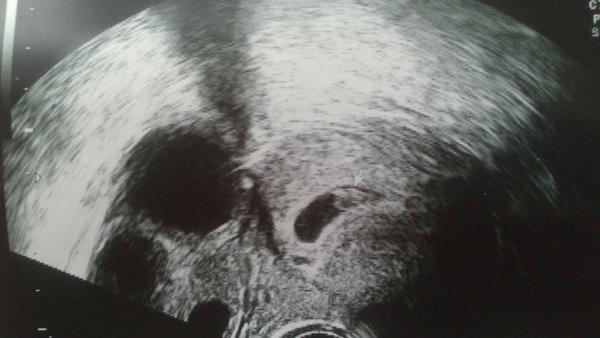

Čaute kočky, tak som chviľočku doma, tak rýchlo malého drobca posielam na pekný dník 🙂 vyvíja sa presne, ako má, má 8,5 mm a termín pôrodu máme 16.7.2012, sme teda v 7.tt 🙂

@kostickabonnie tak bola som u dr. lebo som sa dosť bála a ma ukludnila a spravila mi aj sono či to pichanie nie je cysta ,ale nie ..hladala na sone niečo a našla 5mm dutinku 😅 ešte sa schovávala ,ale je tam 😝 a to pichanie je vaječník ktorý produkuje žlté teliesko a preto to pichanie 😉